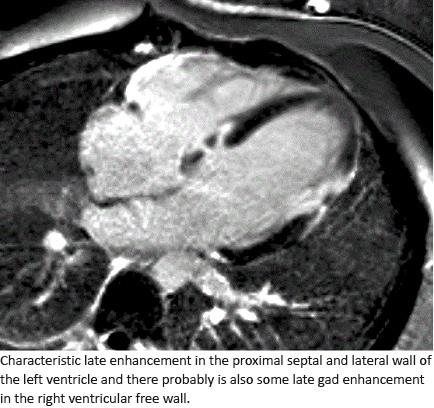

This was a single-centre, retrospective study of patients diagnosed with CS from January 2006 to December 2016 at Rigshospitalet, Copenhagen, Denmark. During the study period, all patients admitted to the Department of Cardiology (including the Department for Lung Transplantation) with a diagnosis of sarcoidosis (International Classification of Diseases (ICD)-10 DD86), were identified using the hospital’s electronic filing system. The medical records of the patients were reviewed systematically and examined in order to identify patients with cardiac involvement. Patients were selected for review if it was documented that they had cardiac findings or symptoms, i.e. dyspnoea, syncope, palpitations, chest pain, fatigue or dizziness, and were included if fully or partially fulfilling the diagnostic criteria for CS as presented by the Japanese Ministry of Health and Welfare (JMHW) from 1993 [6] or the modifications hereof [7]. We also included patients with ventricular tachycardia (VT), complete heart block or abnormal electrocardiography (ECG) with right-bundle brunch block, left-bundle brunch block, first-degree atrioventricular (AV) block and positive endomyocardial biopsy (EMB) or positive advanced imaging studies such as cardiac MRI, characterised by regional wall motion abnormalities, abnormal wall thickness, myocardial oedema and inflammation using late-gadolinium-enhanced (LGE) images and T2-weighted imaging.

LGE has demonstrated an improved sensitivity for the diagnosing of CS. Smedema et al [12] have compared the JMHW criteria with CMR sensitivity for CS and found that all 12 patients who fulfilled the JMHW criteria had a positive CMR. Patel et al [13] examined the prognostic value of LGE in CMR and demonstrated that patients with LGE had a nine-fold higher occurrence of adverse events with arrhythmias and cardiac death than non-LGE patients. A study by Greulich et al [16] explored a large population of 155 patients with systemic sarcoidosis who were examined by CMR for possible CS. After a follow-up of 2.6 years, they concluded that the presence of positive LGE by CMR was the best independent predictor for potential future lethal events like cardiac death, aborted sudden cardiac death, appropriate ICD therapy or ventricular tachycardia. In our study, 53% of patients were retrospectively diagnosed by positive CMR. Three of the patients in our cohort underwent fluorodeoxyglucose (FDG)-PET and had positive scans. FDG-PET technique may supplement and in some instances replace MRI and will likely play a greater role in the future [17]. It is possible that a proportion of the 180 patients without a CS diagnosis did, in fact, have cardiac involvement. Further studies are required to investigate early or “silent” CS in patients with extra-cardiac sarcoidosis [3, 4] and possibly the new non-invasive techniques will help provide this information